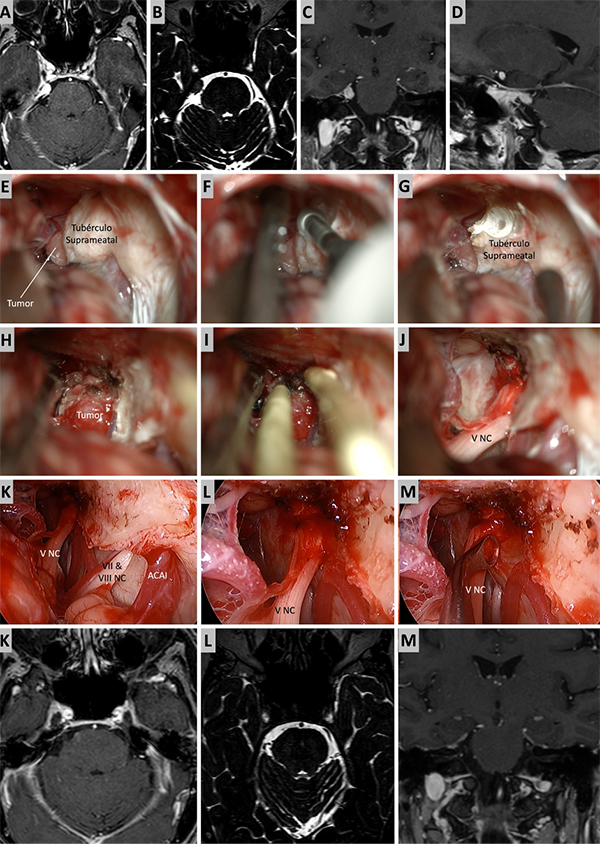

Figura 6. Caso ilustrativo #4. Meningioma de la MRPC con implantación petrosa anterior. El paciente presentaba neuralgia del trigémino atípica derecha. A-D. Imágenes por RMN pre operatorias. E-J. Se realiza un abordaje retrosigmoideo consiguiendo la resección total del tumor. K-M. Con ayuda de endoscopio y lente con angulación de 30º se inspecciona el área sin encontrar remanente tumoral. Se observa liberación del nervio trigémino. K-M. RMN postoperatoria que muestra resección total.